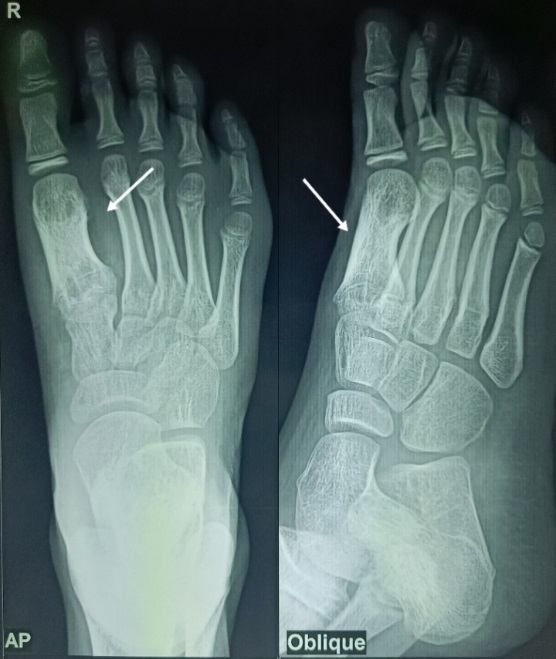

On admission, routine blood investigations like complete blood count, erythrocyte sedimentation rate, bleeding time, clotting time, liver function test, kidney function test and viral markers were sent. His erythrocyte sedimentation rate was mildly raised, but his white blood cell count and other blood tests were within the normal range. A tuberculin skin test was positive, and a chest radiograph was normal. A radiograph of the right foot revealed a centrally placed lytic lesion with an eccentrically located sclerotic lesion in the first metatarsal. The cortices of the first metatarsal were thickened, and the diaphysis was wider than in the other metatarsals. Magnetic resonance imaging study of right foot revealed an altered signal intensity of the first metatarsal, corresponding to the osteolytic lesion with intraosseous abscess, loss of cortex at places and periosteal reaction with fluid signal intensity along the first metatarsal; fluid signal intensity was also noted in the surrounding soft tissue over dorsum and plantar aspect of foot.